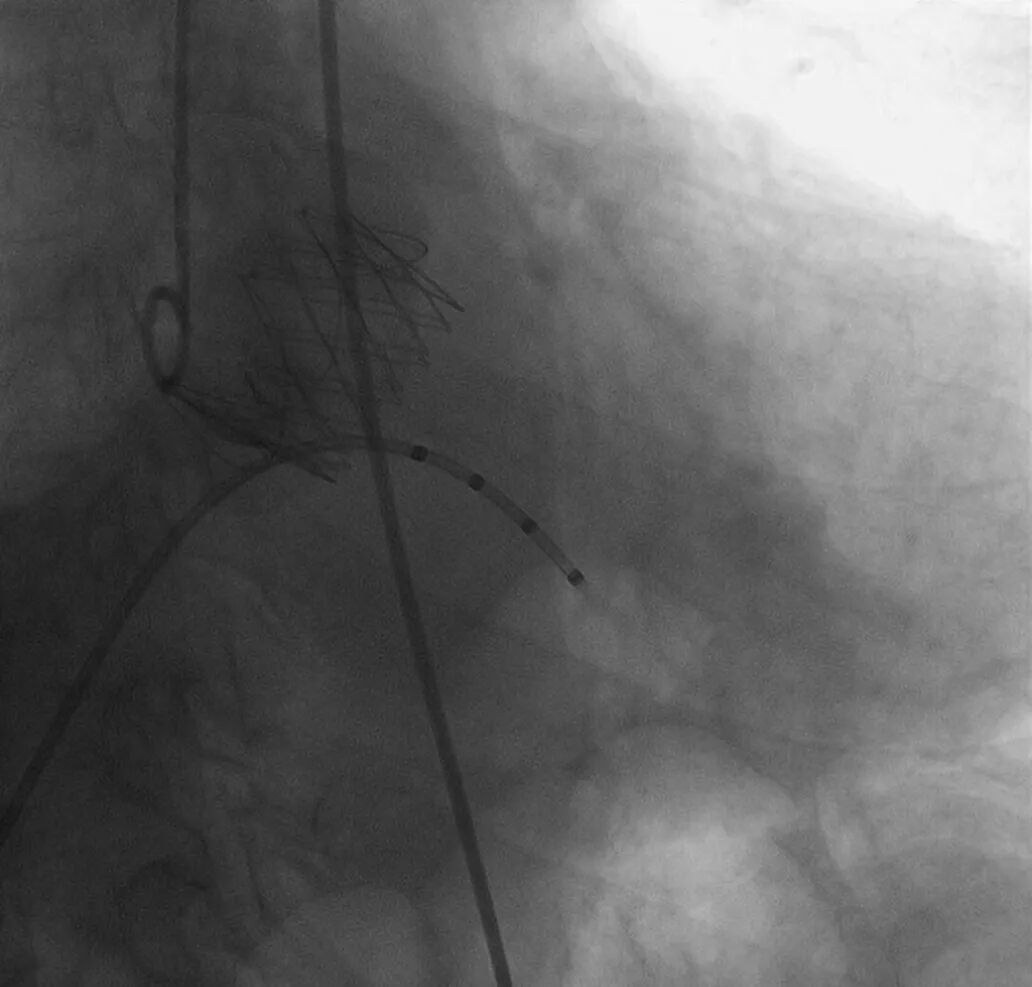

术中,团队凭借丰富的微创介入经验,通过股动脉仅两三毫米的穿刺切口,顺利完成瓣膜定位、释放与固定等一系列关键操作。整个手术过程中,患者血流动力学始终保持稳定,无明显不适。术后即刻超声检查显示,植入的瓣膜功能优异,未出现瓣周漏、反流等并发症,手术取得圆满成功。

瓣膜成功植入